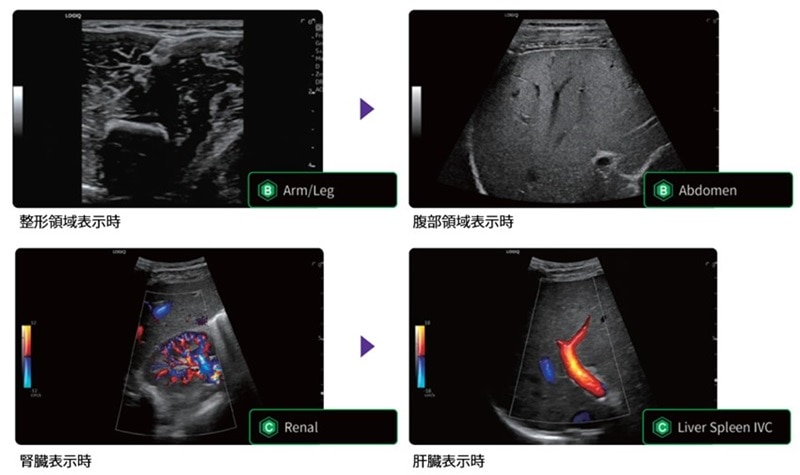

画像を解析した結果から、検査部位に適切な画質設定に切り替える機能や臓器に合わせて適切な血流設定を表示する機能を搭載し、検査の効率化に寄与いたします。ルーチン検査に使用する時間を短縮し、より時間をかけなければならない症例に注力できるよう、検査の効率化・検査時の負担低減を実現いたします。